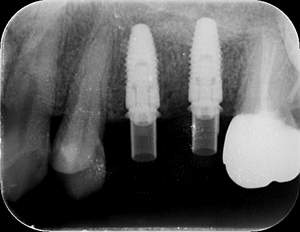

インプラント治療の症例3

レントゲン写真

- Befor

- After

| 年齢 | 50代・男性 |

|---|---|

| 主訴 | 左下7番 |

| 治療内容 | 右下7番インプラント埋入 |

| 治療費 | 合計:572,000円 診断料:55,000円 埋入料:165,000円 サージカルガイド:55,000円 静脈内鎮静麻酔:77,000円 仮歯:55,000円 上部構造(フルジルコニア):165,000円 (2023年1月現在) |

| 治療期間 | 約8ヶ月 |

| リスク・副作用 | リスク・副作用 |

| 治療方針 | 骨が十分にあるため、骨造成をすることなく埋入した。かみ合わせが強いので、負荷がかからないよう、夜寝るときにマウスピースをつけるよう指示をした。 |

| 担当者所見 | 左下6番7番のインプラントは他院で埋入しており、右下7番は抜歯したままで、かみ合わせの歯が落ちてきてしまうのでインプラントを埋入しました。 |